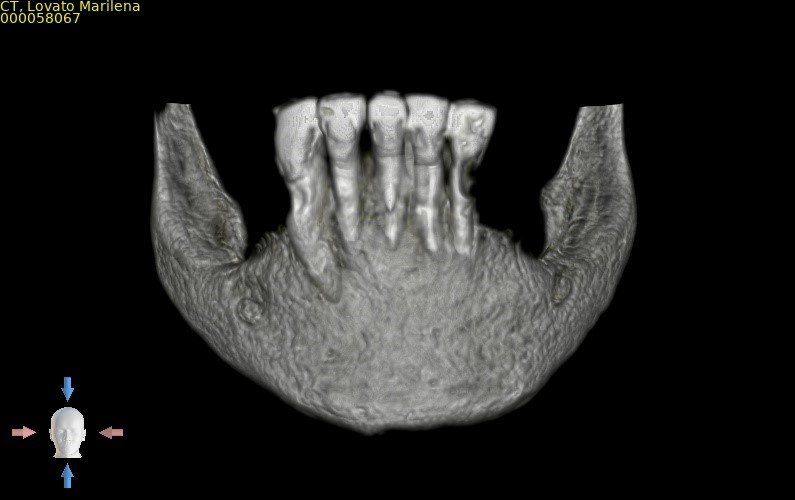

Paciente do sexo feminino, 82 anos, com a presença de dentes anteriores de mandíbula usando prótese móvel na região posterior por mais de 30 anos. Com isso, a reabsorção óssea posterior causou um desnível muito grande em relação à região anterior.

Através do programa Blue Sky (em parceria com a empresa Odontoplanning), foi feito planejamento guiado com 2 guias. O primeiro guia de recorte ósseo, tem como objetivo o recorte e aplainamento ósseo, deixando uma altura óssea mais uniforme entre a região posterior e anterior da mandíbula.

Através da imagem do osso recortado é planejada a guia de perfuração que vai se encaixar de uma maneira perfeita no osso recortado.